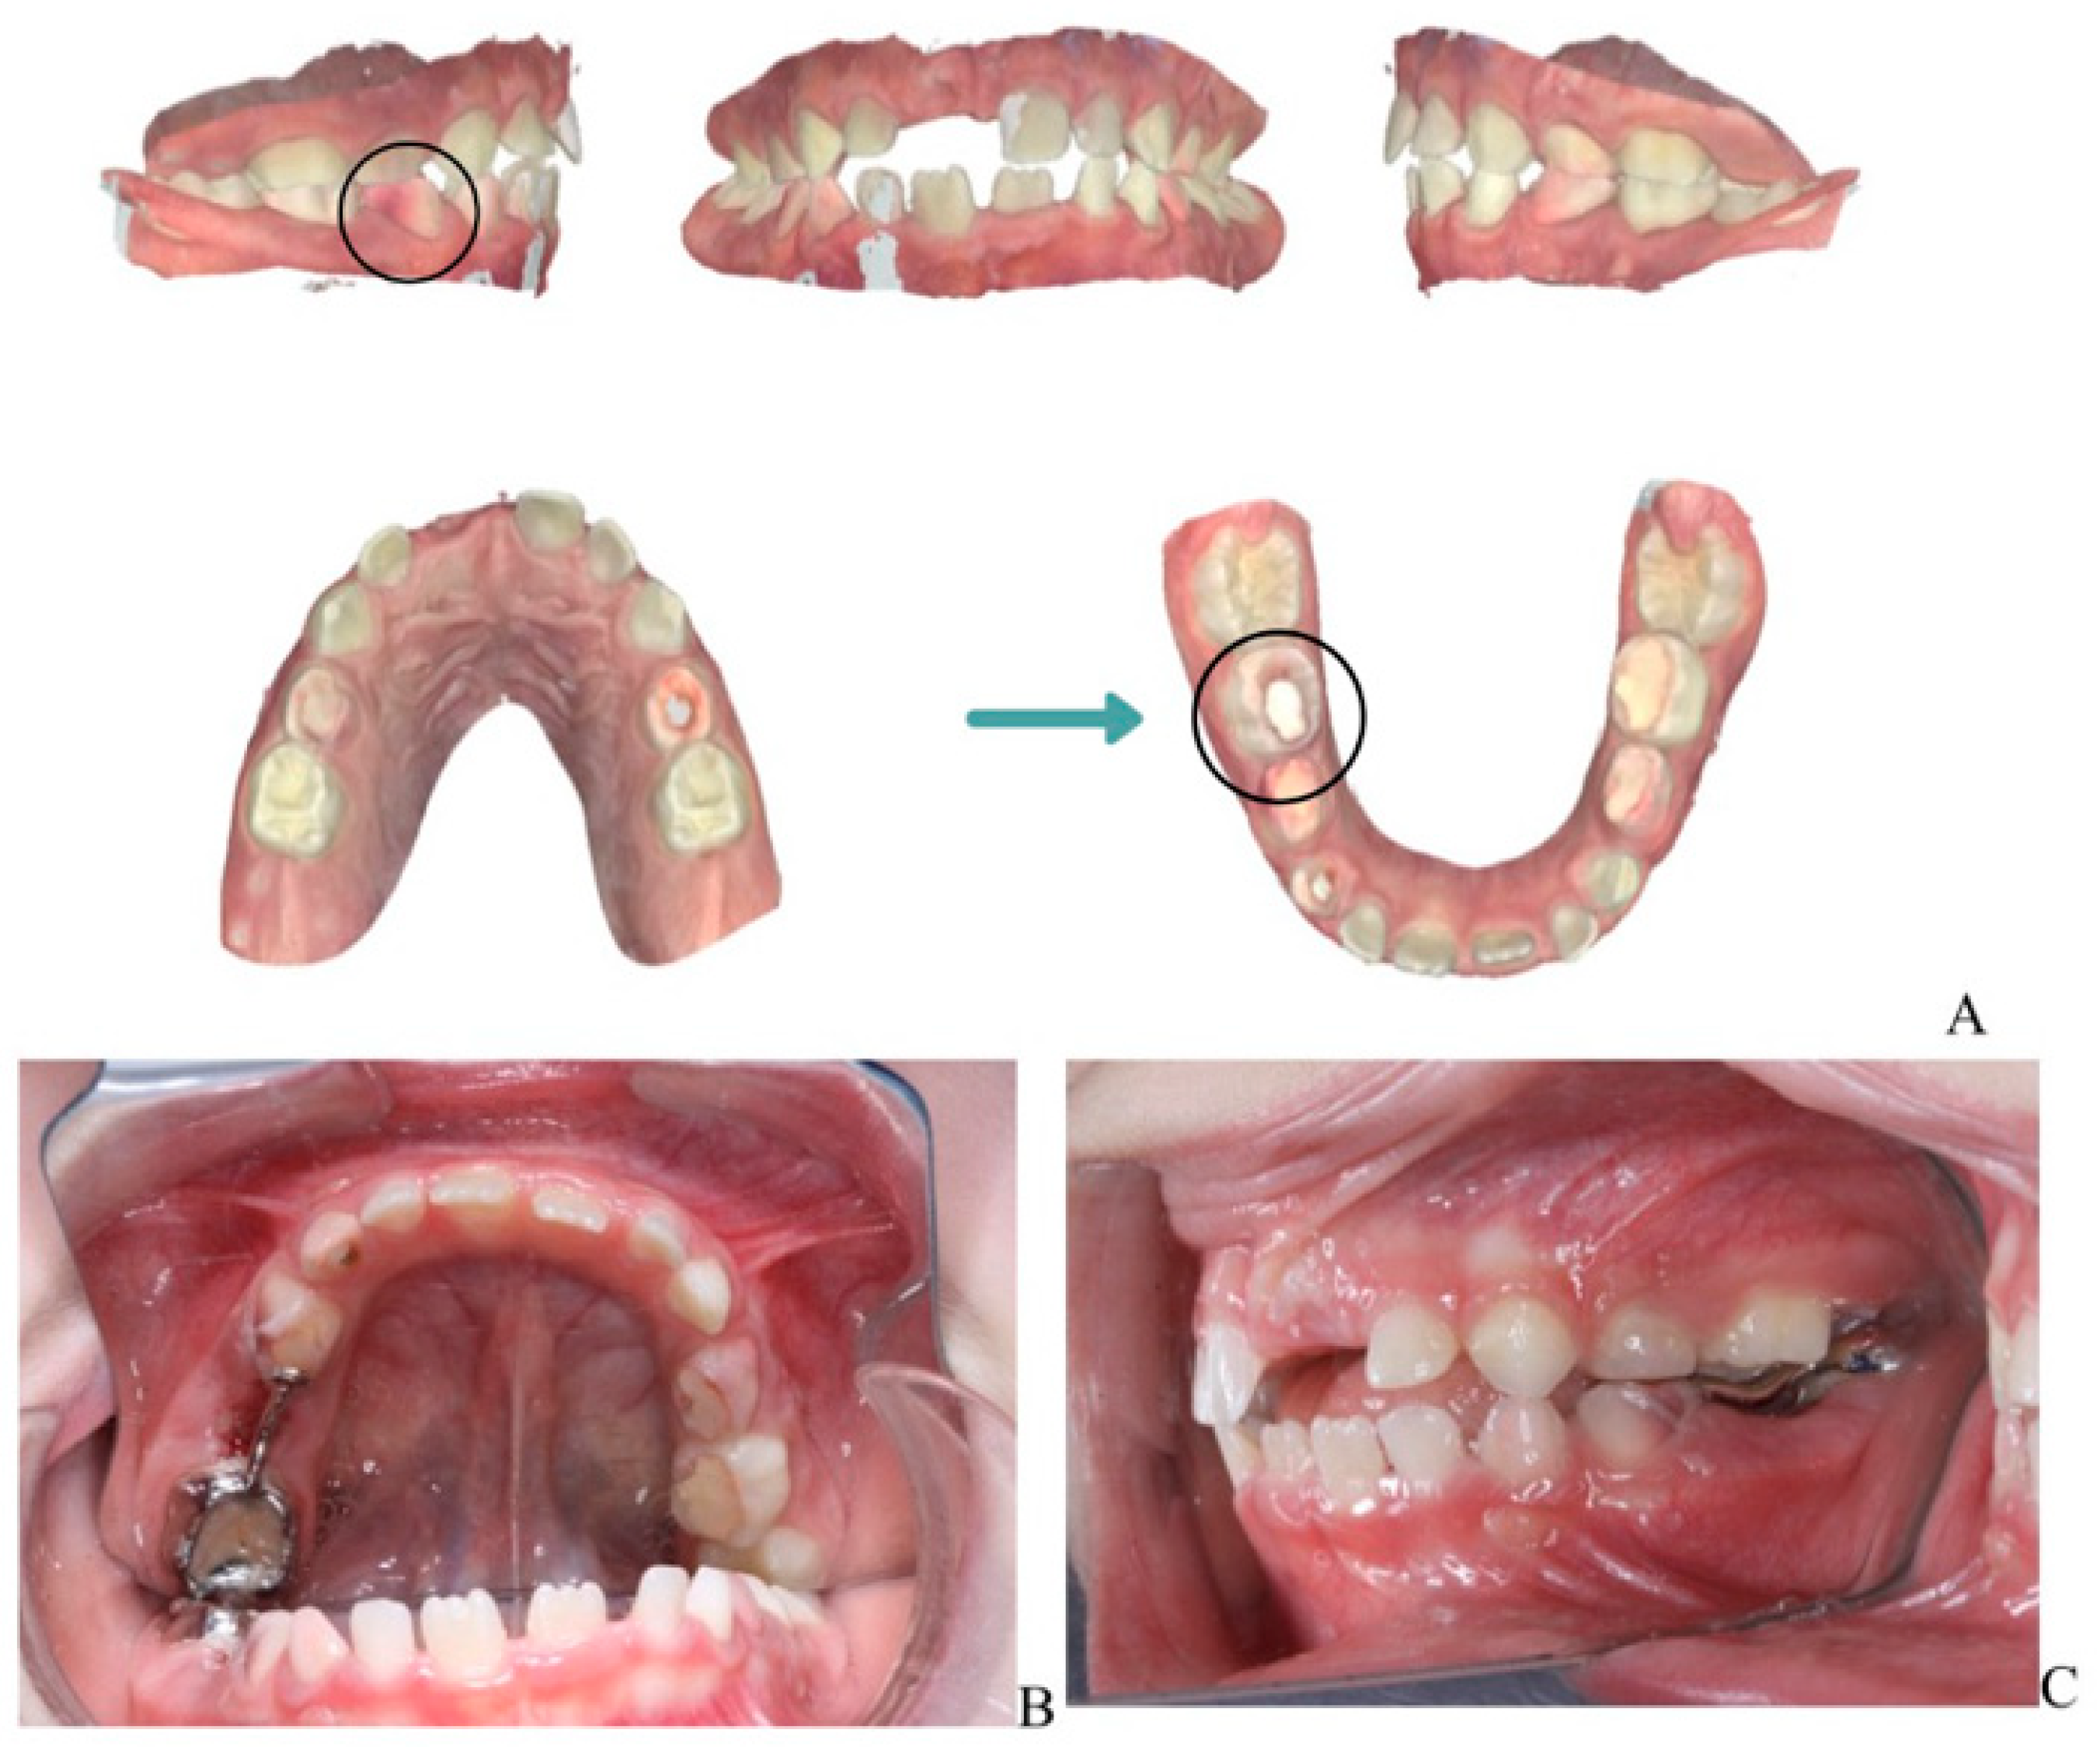

Figure 3.

Orthodontic management following extraction of mandibular right second primary molar (tooth 85). (A) Scanned models of the dental arch showing the area of extraction and planned space maintenance. (B) Indirect intraoral mirror photograph showing the laser-sintered, digitally designed space maintainer cemented in situ to preserve arch integrity and guide eruption of the permanent successor (tooth 45). (C) Indirect intraoral mirror photograph showing a lateral view of the space maintainer, illustrating its position and adaptation to the adjacent teeth.

A laser-sintered digitally designed space maintainer was fabricated and cemented to preserve arch integrity and guide the eruption of the permanent successor (tooth 45) (Figure 3). Ongoing monitoring includes dental, biochemical, and renal assessments every 3–6 months.